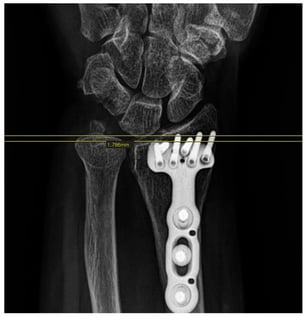

Comparative Study of Radiologic Changes in Ulnar Variance and Ulnolunate Distance After Distal Radius Fracture Surgery: Patients with vs. Without Lunate Ulnar Corner Cysts

Surgeries 2026, 7(1), 39; https://doi.org/10.3390/surgeries7010039 - 17 Mar 2026

Background: Subchondral cysts at the ulnar corner of the lunate are frequently encountered in patients with distal radius fractures. We hypothesized that the presence of these lunate subchondral cysts may be associatedwith decreased cortical bone density due to limited load translation. Consequently, this

Background: Subchondral cysts at the ulnar corner of the lunate are frequently encountered in patients with distal radius fractures. We hypothesized that the presence of these lunate subchondral cysts may be associatedwith decreased cortical bone density due to limited load translation. Consequently, this could lead to lunate fossa collapse and increased ulnar variance following fracture fixation. Methods: A retrospective analysis was performed on 176 patients who underwent open reduction and internal fixation using the Double-tiered Subchondral Support (DSS) procedure between May 2014 and June 2017. Twenty-eight patients identified with lunate subchondral cysts on preoperative CT scans were selected as the study group. A control group of 28 patients without cysts was selected using matched-pair analysis, controlling for gender, age, fracture classification, and follow-up period. Results: The mean change (delta) in ulnar variance was 0.191 mm in the cyst group, which was less than the 0.233 mm observed in the control group; however, this difference was not statistically significant (p = 0.557). Regarding ulnolunate distance, the cyst group showed a mean change (delta) of 0.991 mm, while the control group showed a change of 1.123 mm. This difference was also not statistically significant (p = 0.681). Conclusions: Although it was hypothesized that lunate subchondral cysts might limit load translation to the radius and compromise cortical bone density—potentially affecting fracture healing and the maintenance of reduction—our statistical analysis did not support this hypothesis. The presence of lunate subchondral cysts did not significantly increase the risk of lunate fossa collapse or ulnar variance progression compared to the control group.